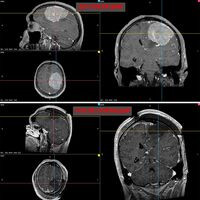

В Новосибирске врачи удалили 35-летнему пациенту гигантскую опухоль головного мозга. Об этом сообщает пресс-служба НМИЦ имени Мешалкина Минздрава России.

В ноябре прошлого года у мужчины появилась слабость в правой руке и затруднения речи — МРТ выявила у него менингиому диаметром более восьми сантиметров в левом полушарии мозга. К концу года рука практически перестала работать, ходьба давалась пациенту с трудом.

Пятичасовая операция прошла успешно. Опухоль удалили полностью. Уже на следующий день появились движения в руке, через две недели пациент снова стал сам ходить. У него восстановились речь и движения, приступы исчезли.